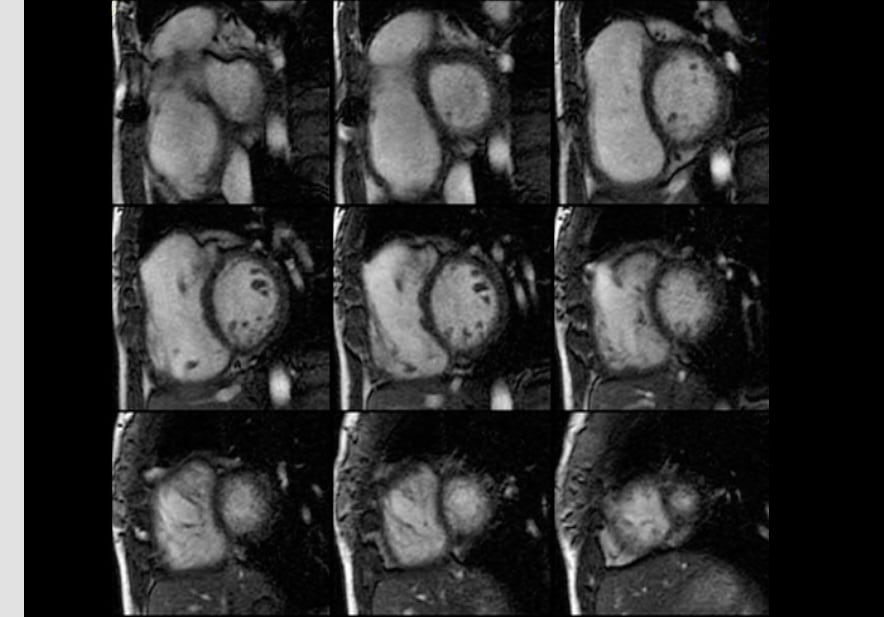

Role of cardiac MRI in the assessment of cardiac amyloidosis

Role of cardiac MRI in the assessment of cardiac amyloidosis — Although biopsy is still the gold standard of diagnosis for patients with suspected cardiac amyloidosis, noninvasive cardiac MRI offers superior abili[...]